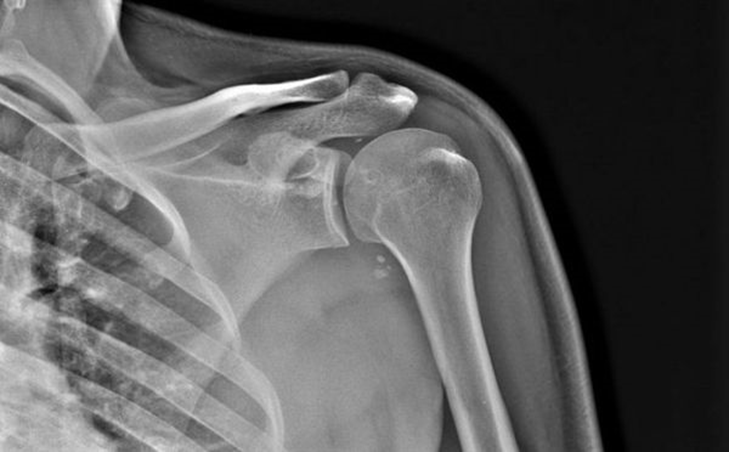

Запитання 18

РОЗПІЗНАЙТЕ НА РЕНТГЕНОГРАМІ СУГЛОБ, ЩО МАЄ МІЛКУ СУГЛОБОВУ ЗАПАДИНУ І СКРІПЛЕНИЙ ПЕРЕВАЖНО М'ЯЗАМИ, ТОМУ ТУТ ВІДНОСНО ЧАСТО БУВАЮТЬ ВИВИХИ.

варіанти відповідей

Запитання 20

НА ЯКИЙ СУГЛОБ ВКАЗУЄ СТРІЛКА НА РЕНТГЕНОГРАМІ? КІСТКИ ЯКОГО ВІДДІЛУ СКЕЛЕТУ ВІН З'ЄДНУЄ?

ГРУДНИННО-КЛЮЧИЧНИЙ С.

ПЛЕЧОВИЙ С.

НАДПЛЕЧОВО-КЛЮЧИЧНИЙ С.

АКРОМІАЛЬНО-КЛЮЧИЧНИЙ С.

КІСТКИ ВЕРХНЬОЇ КІНЦІВКИ

КІСТКИ ТУЛУБА І ВЕРХНЬОЇ КІНЦІВКИ

Запитання 21

РОЗПІЗНАЙТЕ НА РЕНТГЕНОГРАМІ СУГЛОБ, ЩО СКЛАДАЄТЬСЯ З ТРЬОХ СУГЛОБІВ, ЯКІ МАЮТЬ СПІЛЬНУ КАПСУЛУ.

РОЗПІЗНАЙТЕ НАЙРУХОМІШИЙ СУГЛОБ ТІЛА ЛЮДИНИ, А ТАКОЖ СУГЛОБИ І КІСТКИ З ПЕВНИМИ ДІАГНОЗАМИ.

Запитання 46

ДЕ ВИ БАЧИТЕ СУГЛОБ, ЩО ЗАБЕЗПЕЧУЄ РУХИ ПЛЕЧА?